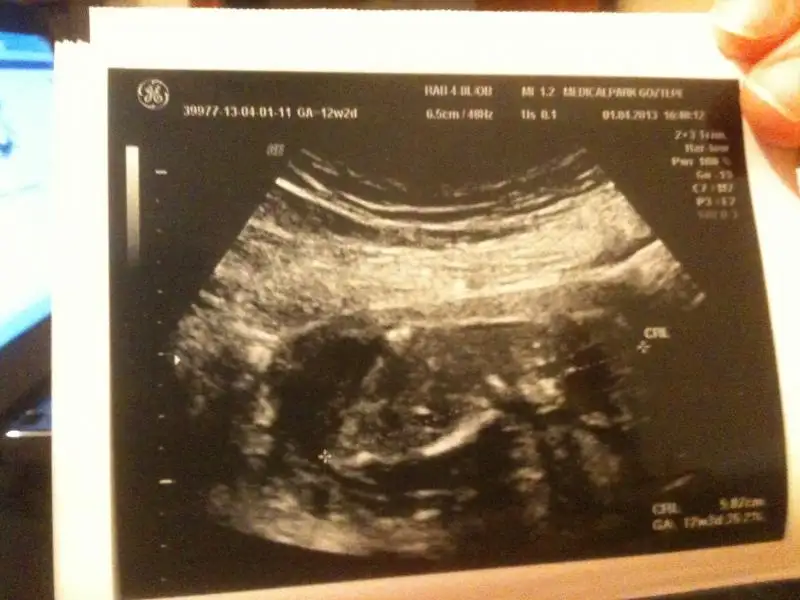

kızlar bakın bu bacak arası görüntüsü bebeğimin pipi resmi diye verdi doktor sizcede pipi mi kordon olabilirmi

arkadaşlar dün doktoora gittim ancak doktor yüüstü yatmış dedi bu resmi verdi orkiş birşey belli oluyor mu?